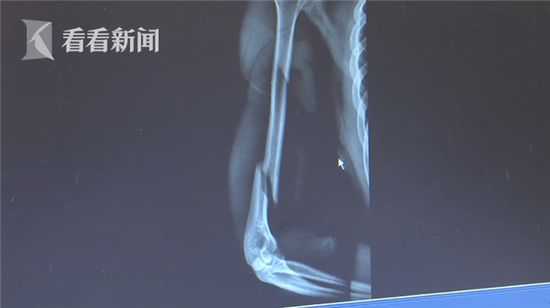

长沙市中心医院创伤手外科主治医师蒋亮东表示,“从照片看出这是一个长的螺旋形骨折,比如投掷铅球,扳手腕这些间接暴力引起的。”